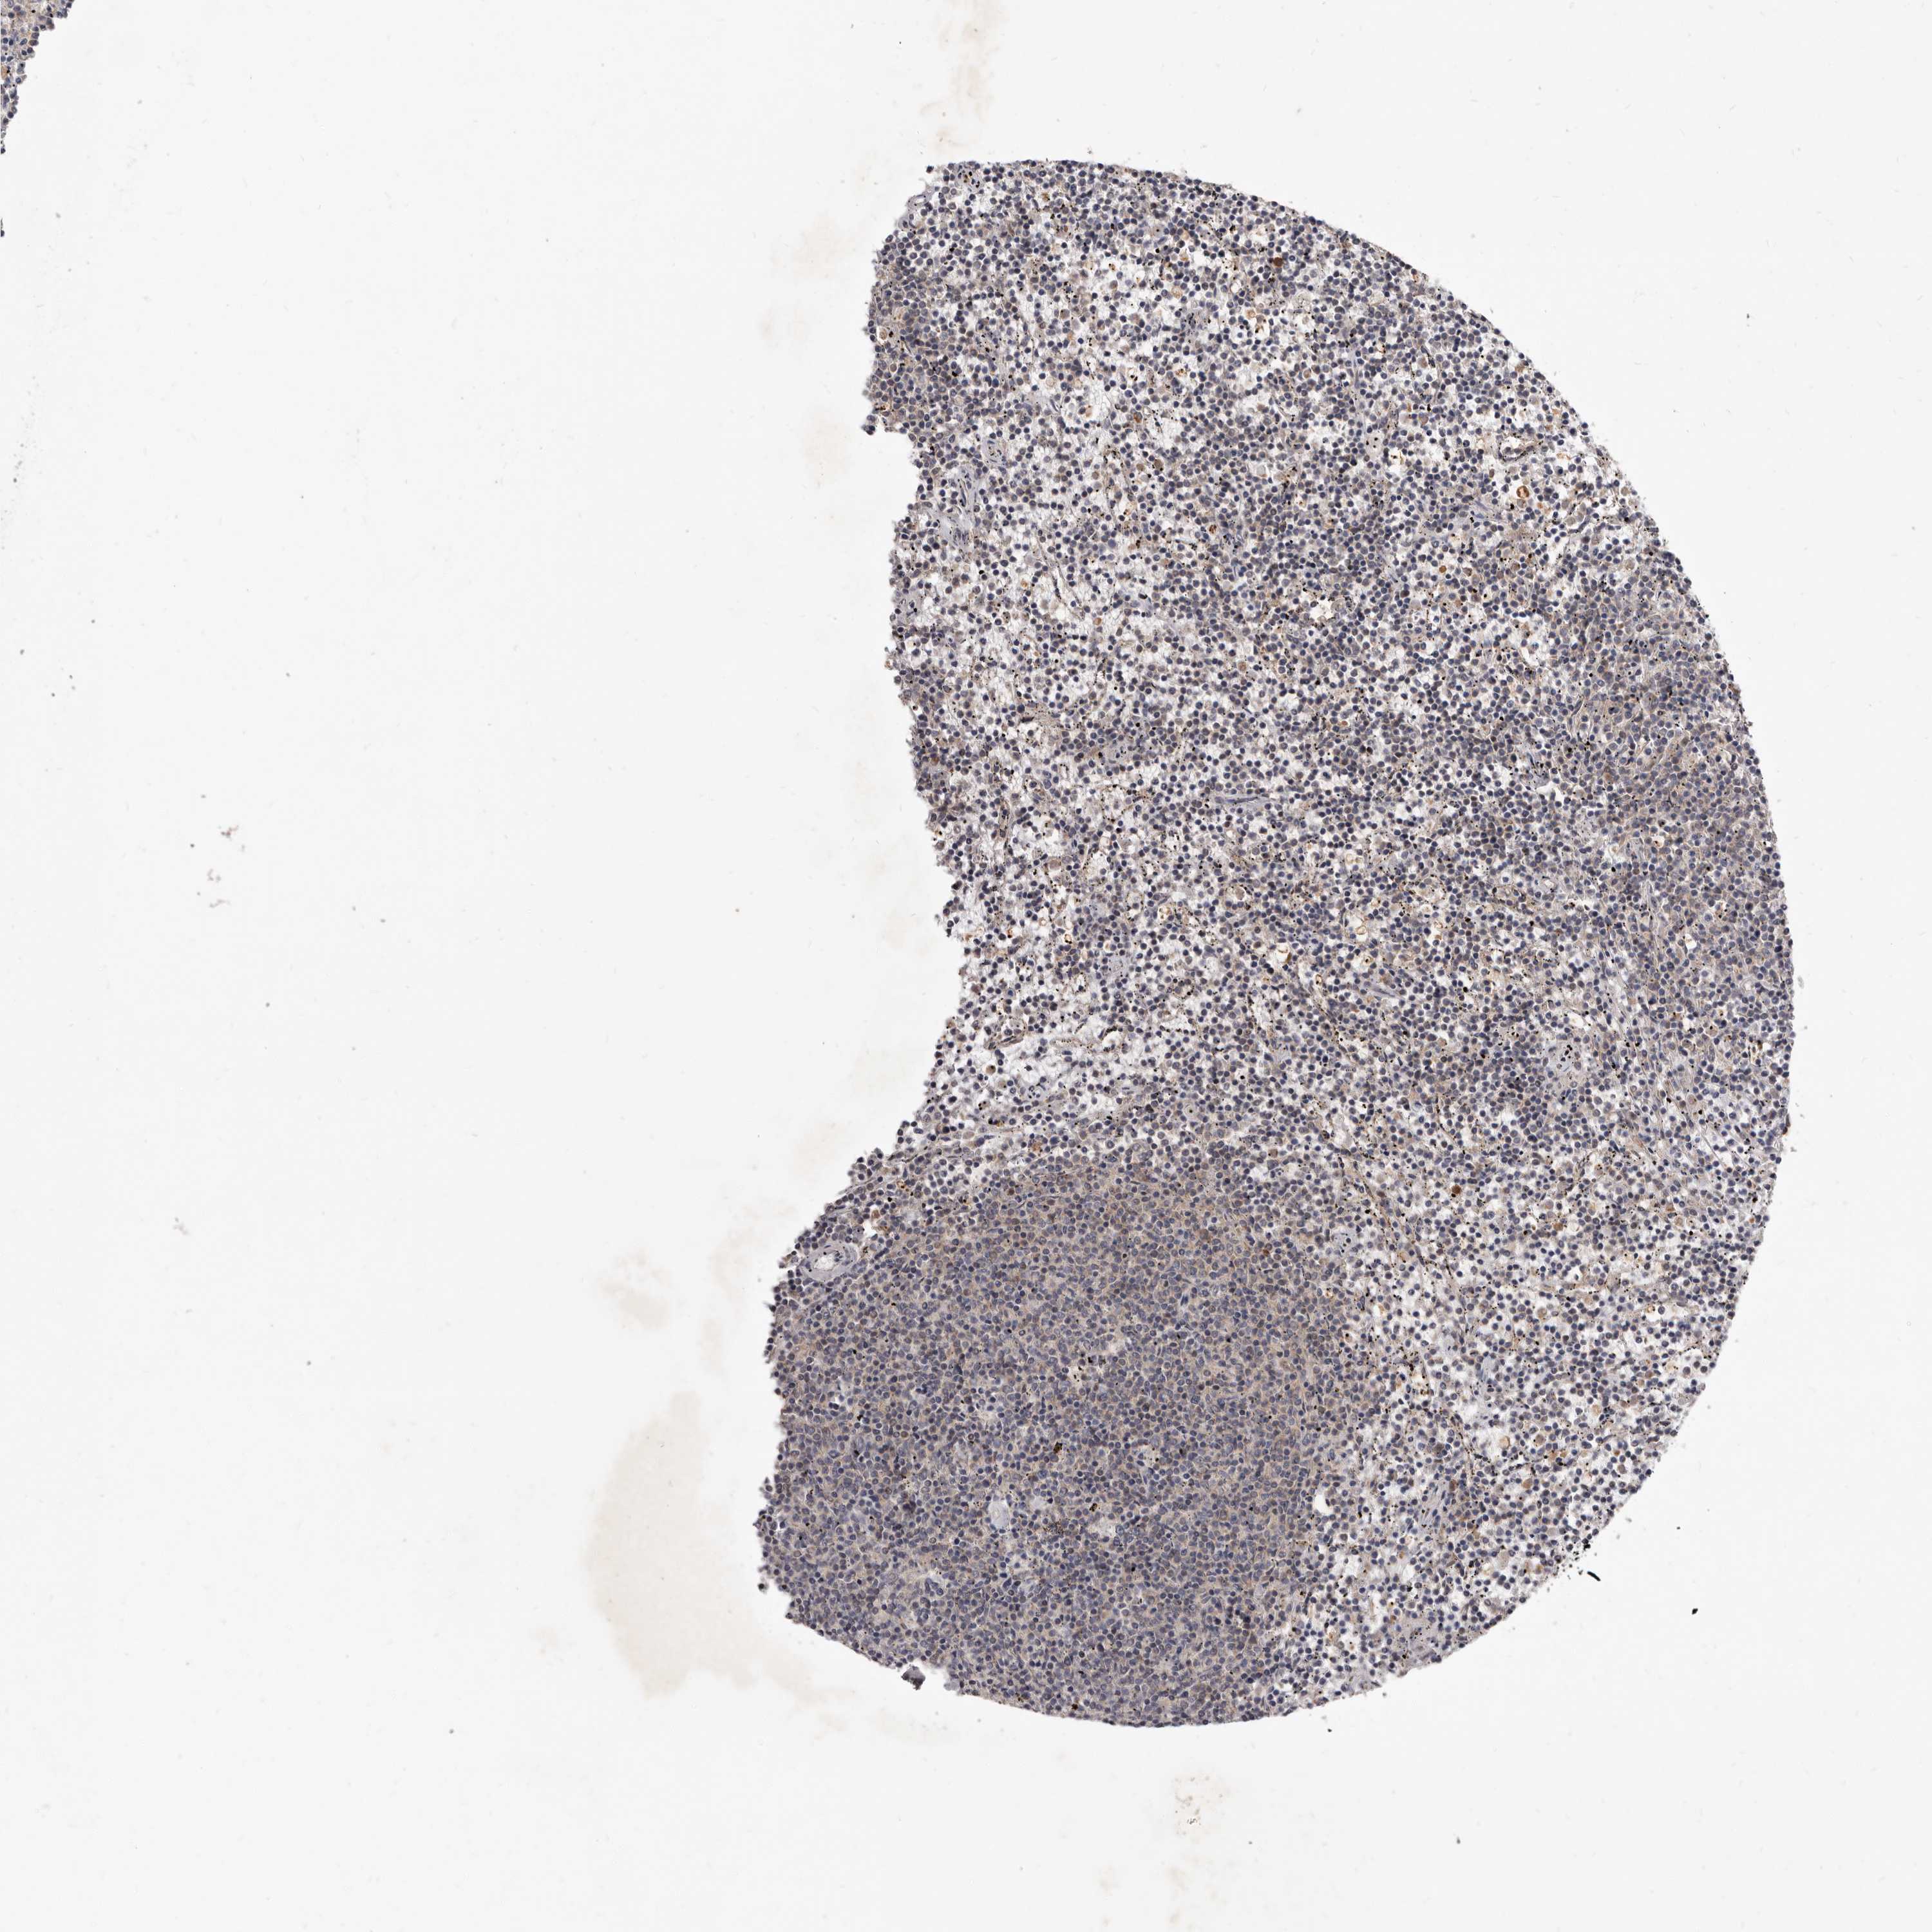

CANCER LYMPHOMA Show tissue menu

LYMPHOMA - Protein expressioni

A mouse-over function shows sample information and annotation data. Click on an image to view it in a full screen mode. Samples can be filtered based on level of antibody staining by selecting one or several of the following categories: high, medium, low and not detected. The assay and annotation is described here.

Antibody stainingi

Antibody staining in the annotated cell types in the current human tissue is reported as not detected, low, medium, or high, based on conventional immunohistochemistry profiling in selected tissues. This score is based on the combination of the staining intensity and fraction of stained cells.

Each image is clickable and will lead to virtual microscopy that enables deeper exploration of all samples and also displays staining intensity scores, fraction scores and subcellular localization as well as patient and tissue information for each sample.

HPA022434

Staining

Medium

Low

Intensity

Moderate

Quantity

75%-25%

Location

Nuclear

Hodgkin's disease, NOS

Malignant lymphoma, non-Hodgkin's type, High grade

Malignant lymphoma, non-Hodgkin's type, Low grade